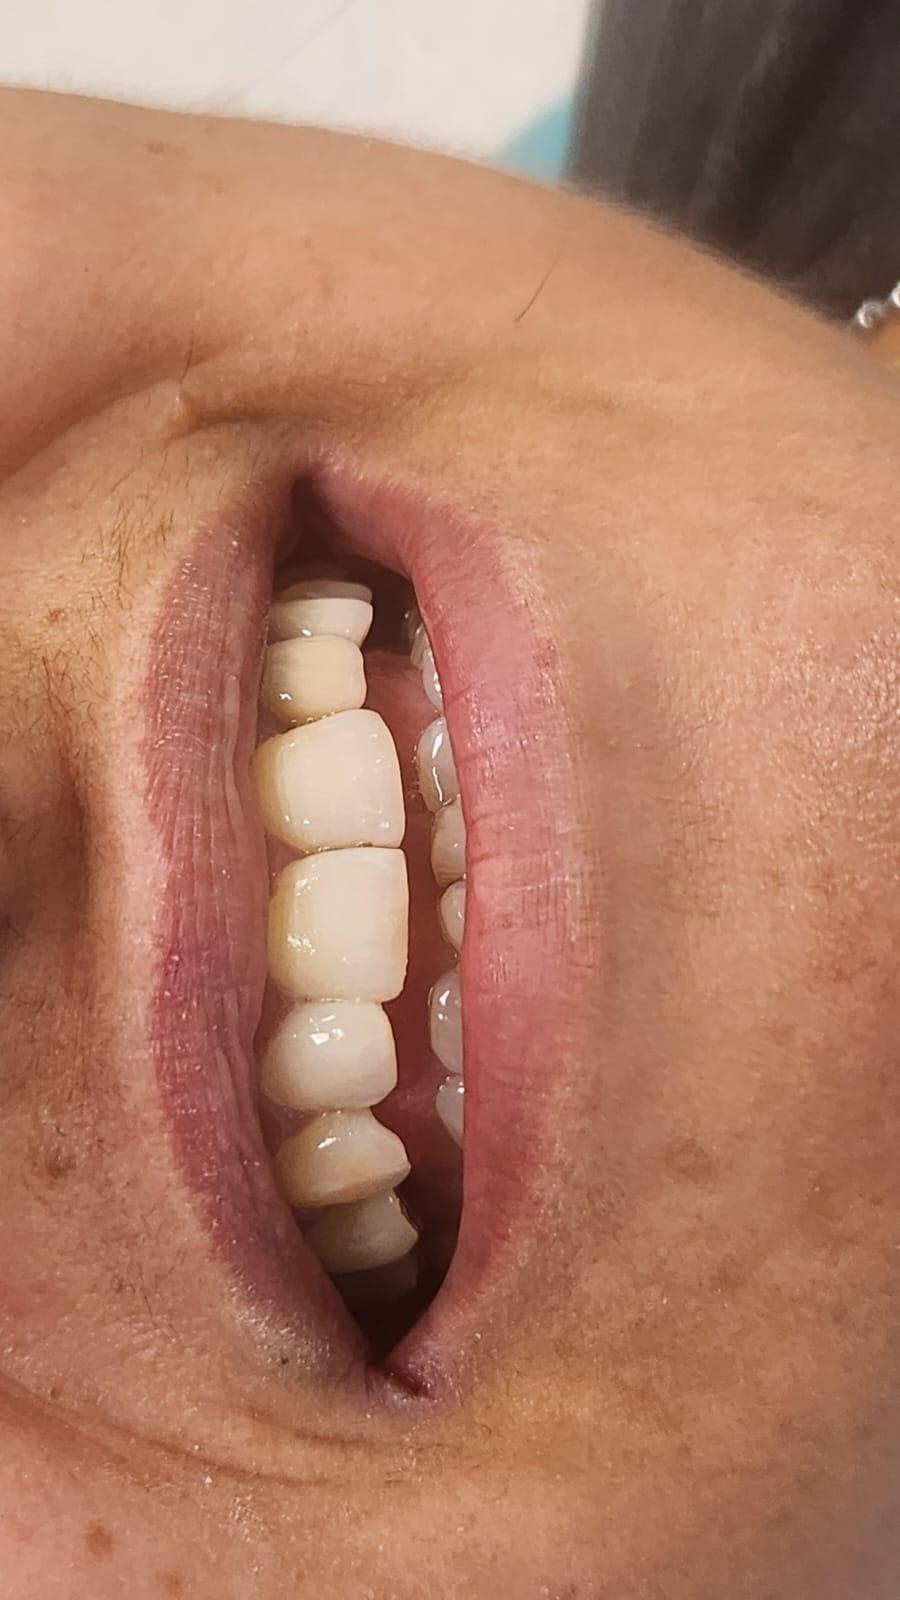

La Clinica LUY ESTHETIC ART se fac tratamente stomatologice pentru remedierea unui zambet perfect prin intermediul aparatului dentar. Pacientii au la dispozitie numeroase tipuri de aparate dentare, in functie de preferinte, necesitate si costuri. Pentru ca modificarile necesare sa se faca intr-un timp mai scurt, este necesara purtarea lui de la varste fragede, cand oasele nu sau dezvoltat complet.

Pot folosi aparate dentare si adultii, deoarece reprezinta cea mai buna varianta de indreptare a problemelor prezente la nivelul cavitatii orale, dar si de natura estetica. Medicul ortodont recomanda aparate dentare in urmatoarele cazuri: dinti strambi sau inghesuiti, dantura cu multe spatii, persoanele care au diastema (strungareata), dificultati la mestecarea alimentelor.

In acest timp are loc procesul de integrare in formatiunea osoasa. Succesul integrarii implantare este dat de catre formarea unei cantitati suficiente de celule osoase in jurul implantului dentar. In functie de necesitatile functionale sau estetice ale pacientului, urmeaza etapa protetica de realizare a lucrarilor de ceramica sau zirconiu. Implantul dentar este foarte important deoarece oasele maxilare se resorb, iar structura fetei incepe sa se modifice. In lipsa dintilor, atat masticatia cat si estetica au de suferit. O igiena necorespunzatoare, fumatul, bruxismul, etc., sunt factori de risc care duc la deteriorarea implantului. In perioada urmatoare dieta pacientului trebuie sa fie moale si la temperatura camerei.